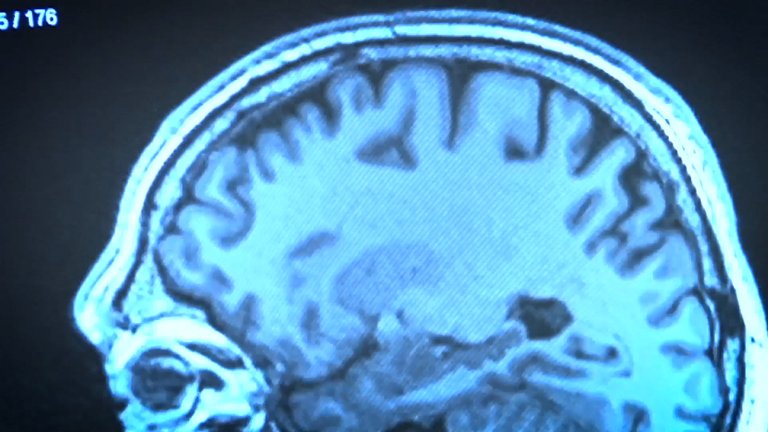

We will also be at the BCBL research center in San Sebastian. A project has been initiated to determine whether bilingualism is a cognitive protection against dyslexia. This project studies the brain of bilingual children. On the other hand, the fact that the mother tongue is a minority language has its nuisances and directly affects the Basques. For example, there is a lack of material created in Basque for the evaluation of language disorders, according to the experts of My Clinic. But the solution may be close: The UPV/EHU opened last year the degree in Speech Therapy in Basque at the San Sebastian campus.